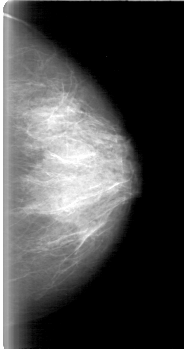

D_4018_1.LEFT_CC

LEFT_CC LINES 5221 PIXELS_PER_LINE 2746 BITS_PER_PIXEL 12 RESOLUTION 43.5 NON_OVERLAY